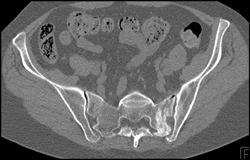

Stress Fracture Sacrum